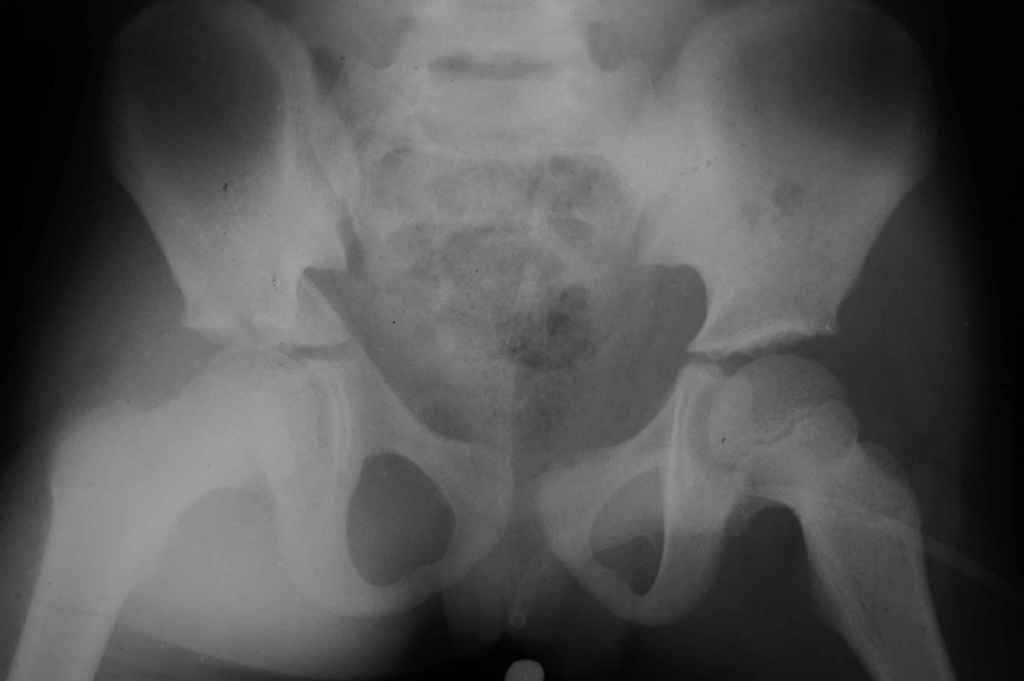

Уважаемые коллеги, помогите определиться с тактикой лечения. Ребёнок 7 лет, травма 11.09.08, поступил с травматическим вывихом бедренной кости.

Вывих вправлен, конечность фиксирована на скелетном вытяжении. Что делать с переломом подвздошной кости? Лечить консерватино или оперировать?